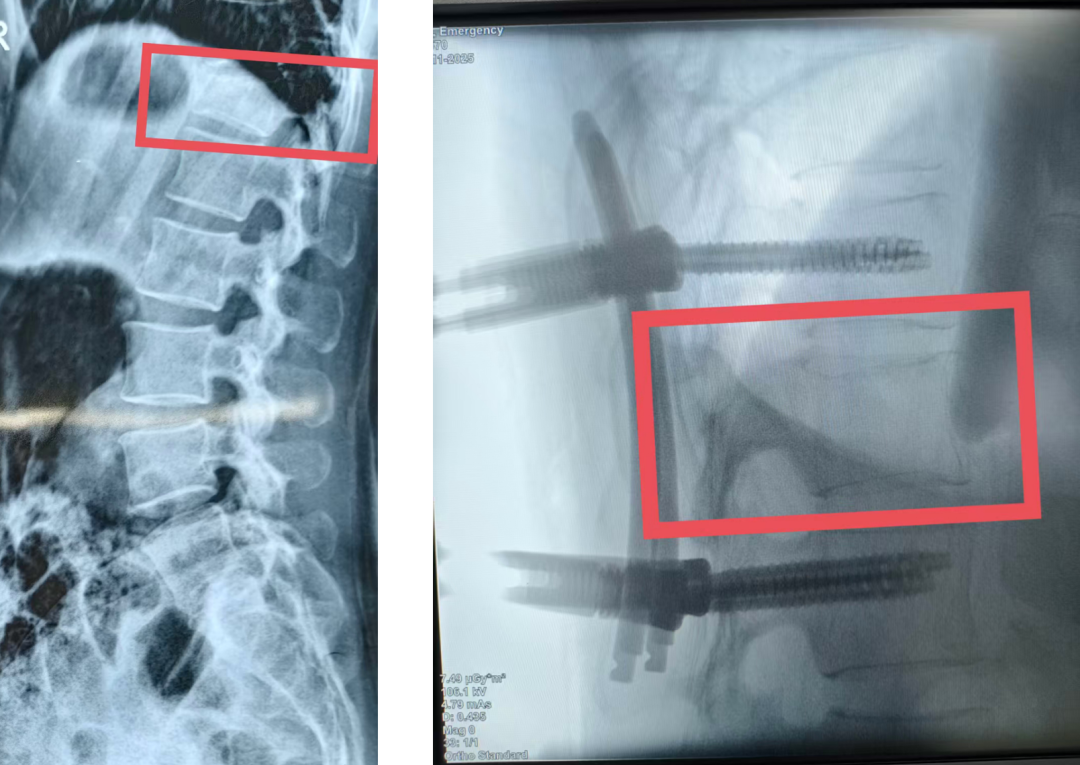

7天前,刘女士在家门口擦车时不慎滑倒,重重坐地,腰背部瞬间剧痛难忍,无法动弹。家人紧急将其送往当地医院,检查结果显示为胸12椎体压缩性骨折,这意味着第12胸椎被压扁。此后,刘女士生活被困在床上,翻身都成奢望,更无法下地行走,日常起居全依赖家人照料,曾经的独立与活力消失殆尽。

在当地医院建议下,刘女士来到西安市中心医院经开院区骨科门诊。刘邦定主任仔细查看片子、认真评估病情后,为其制定了经皮椎弓根螺钉内固定术方案。刘主任耐心解释:“传统开放手术如同修房子要拆墙才能看到内部,而我们的微创手术只需通过几个‘钥匙孔’,就能精准放置‘钢筋’(螺钉),为被压扁的胸椎搭建稳固支架,助其恢复正常高度。”此手术仅需在皮肤上切4个长约1.5厘米的小口子。

手术当天,在刘主任主刀下,经开院区骨科团队配合默契。螺钉被精准置入预定位置,整个手术过程用时短、出血量极少。